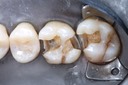

Photos of Clinical Operations

Drs. Peter Kearney, Terry McKay, John St. Germain, and Laurie Vanzella - Mentors